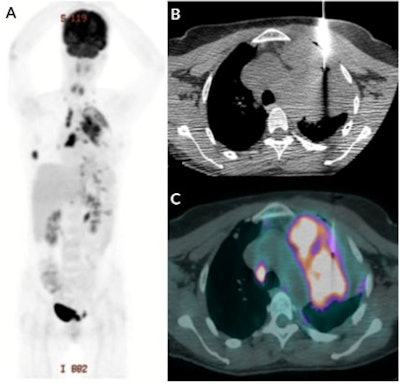

To fill that void, Cerci and colleagues analyzed results from 216 patients (mean age, 65.9 ± 12.1 years) who underwent FDG PET/CT-guided percutaneous biopsy and 125 patients (mean age, 65.4 ± 13.2 years) who underwent the same procedure using CT only as the guide. All 341 subjects underwent whole-body biopsies on the same PET/CT system (Discovery STE-16, GE Healthcare), which featured a CT fluoroscopic imaging system. They then were followed for a minimum of six months.

"Once we integrate CT's excellent anatomical information, especially important to evaluate vessels and important structures related to the biopsy path, with the metabolic characterization provided by FDG-PET images, sampling from the hypermetabolic portion of the apparently larger morphological lesion seen on CT becomes feasible, which is more likely to yield representative material for microscopic analysis," Cerci and colleagues wrote.